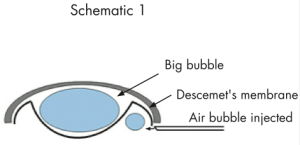

– Ceratoplastia Lamelar Anterior Profunda (DALK)

Segundo o Dr. Gustavo Bonfadini, especialista nesta técnica cirúrgica e desenvolvedor de material cirúrgico para melhorar o resultado desta técnica: “O Transplante Lamelar Anterior Profundo é realizado, preservando-se a camada interior da córnea – chamada de endotélio. Essa técnica é importante, por diminuir a probabilidade de rejeição e melhorar os resultados quando comparada a técnica cirúrgica tradicional.” Retira-se somente o estroma corneano (a parte doente da córnea), mantendo-se a membrana de Descemet e o Endotélio. A técnica conhecida como “Big Bubble”, na qual se separa a membrana de Descemet do estroma utilizando uma bolha de ar é a mais utilizada.

A técnica conhecida como “Big Bubble” (Grande Bolha), é mais difícil de ser realizada, mas representa uma boa opção quando a parte interna da córnea (endotélio) está saudável.